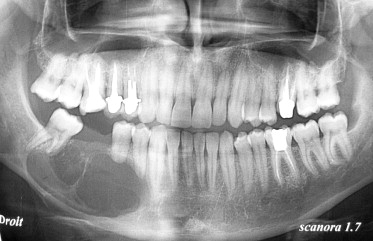

Imagerie en odontologie S3

Imagerie en odontologie S5

Imagerie en odontologie